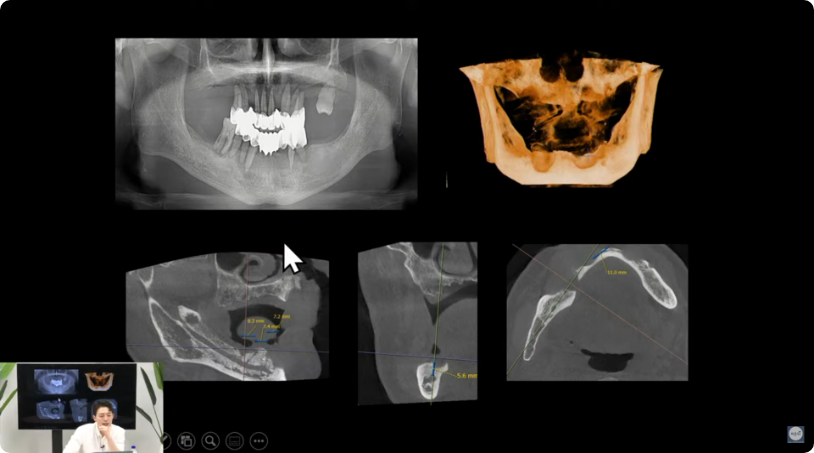

더굿모닝치과는 실제 수술 전, 3차원 3D-CT를 이용하여

정밀진단과 가상수술을 통해 임플란트를 식립할 위치, 방향, 깊이 등

환자 개인의 수술 조건을 사전에 파악하여

한 치의 오차 없이 정확하고 빠르게 완성합니다.